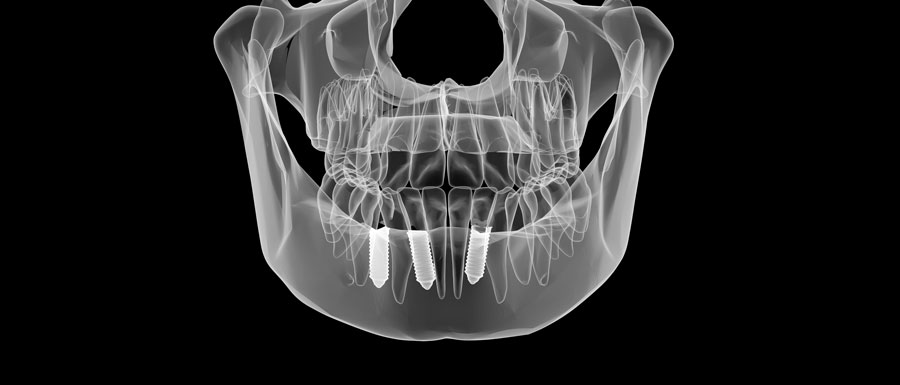

Ambos procedimientos se aplican al maxilar superior. En muchos pacientes observamos un hueso notablemente blando y/o incluso hueco. Esta combinación de hueso blando y hueco provoca que los implantes convencionales no sean fuertes y seguros, y debemos hacer algo para aumentar esa fuerza y poder colocar implantes dentales. Mediante una exploración 3D detectamos aquellos pacientes faltos de hueso. En este momento es cuando aparecen las dos opciones: reconstruir o injertar hueso, o colocar implantes en el pómulo, los conocidos como cigomáticos.

Habitualmente nos decantamos por el implante cigomático cuando es necesario reemplazar el conjunto completo de los dientes superiores. Esto permite que todos los dientes se conecten en forma de arco, aportando la fuerza y la rigidez en un sistema donde cada implante se fortalece como una pieza natural, además se trata de un procedimiento de carga inmediata, el mismo día de la cirugía el paciente ya luce su nueva sonrisa. En injerto óseo de levantamiento de seno lo utilizamos cuando se reemplaza solamente los molares o cuando no hay suficiente altura ósea en el maxilar superior para colocar un implante dental. A veces, dependiendo de cada caso, podemos utilizar un implante cigomático por lado o a veces dos por cada lado. En ocasiones incluso se puede utilizar un implante cigomático a un lado y aumentar el seno del lado opuesto. No siempre es necesario colocar los implantes de forma simétrica, de hecho nuestros cuerpos no lo son. Tanto en los implantes cigomáticos como los de injerto de seno, no deben realizarse si el seno sinusal no está sano o taponado. Si esta área esta bloqueada debemos retrasar el procedimiento hasta que se despeje la obstrucción. Normalmente solamente es necesario algún aerosol nasal.